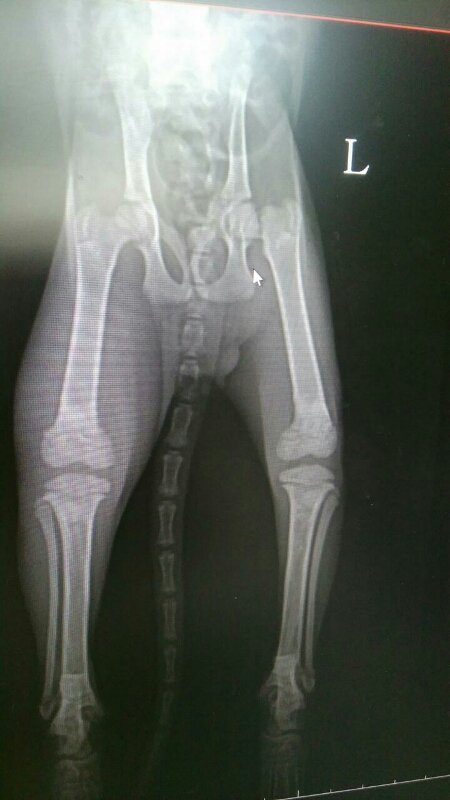

2개월령 0.86키로그램의 작디작은 아이가 오른쪽 다리 골절 왼쪽 고관절 골절 앞두다리도 부러졌다 붙고 있다고 합니다.

엑스레이 사진상으로도 한쪽다리가 많이 부어있습니다.

부러진지 3주정도 됐고 날카로운것에 찔린 상처들이 있다고 하십니다.

염증이 가득차서 많이 부어있고 열감이 느껴집니다.

다른 한쪽은 부러진지 일주일정도 되었다고 하십니다.